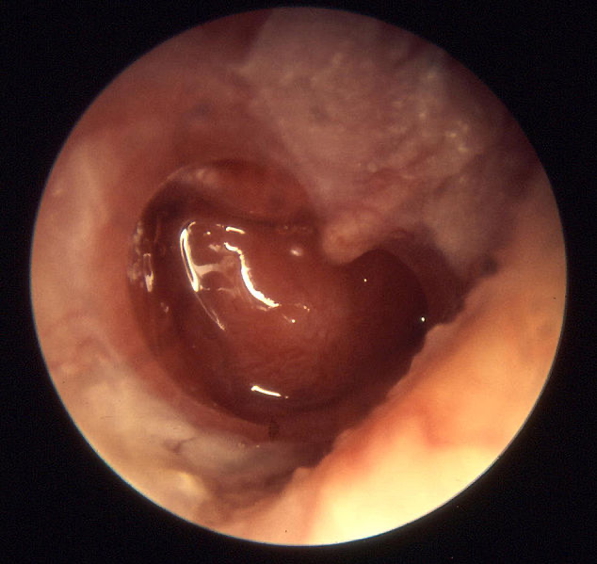

- Otoscopy:

- Tympanic membrane retraction or perforation

- Presence of cholesteatoma

- Scarring and ossicular damage

- Cholesteatoma